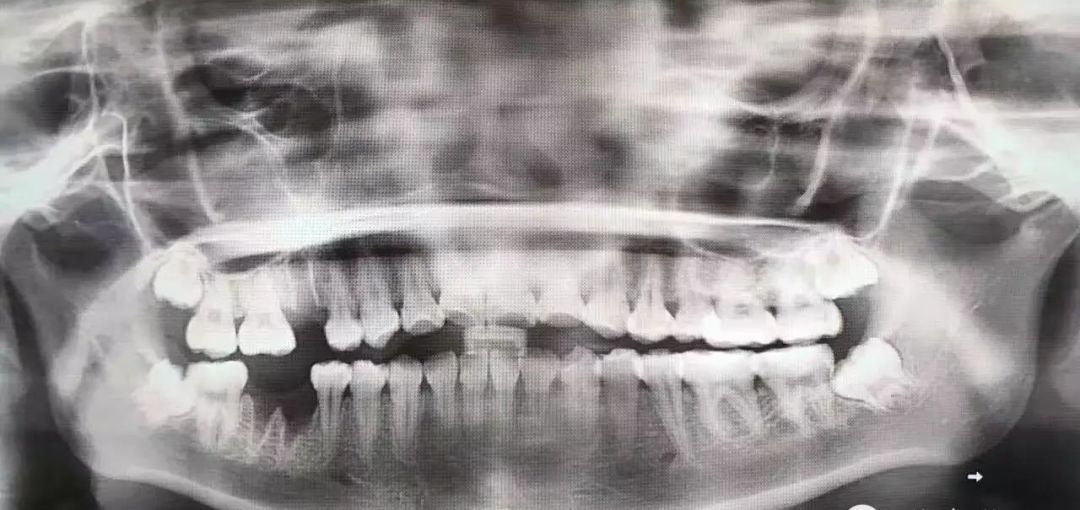

这种款式的横阻生智齿。一般生长情况也分两种,一种是已经出肉的,一种是还未出肉的,操作都差不多,我们就直接看下图的介绍了。

露出牙槽骨后,先削除一部分骨头,露出躺卧如睡美人的横阻生智齿...如果是已经出肉的智齿,就没这一步了。

1.2 恰当检查 包括高质量的X线片,它不仅能提供牙齿的清晰图像,牙根的轮廓和解剖以及牙周骨质情况,还能提供牙齿与邻牙和其他结构之间的关系,其中尤其是下颌骨下缘、下颌骨升支以及下牙槽神经束之间的关系。